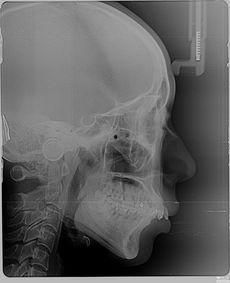

在这些视频中,你可以看到医生们熟练地操作,用专业的工具将牙齿从牙龈中拔出。每一个细节都被清晰地展现出来,让人仿佛置身于牙科诊所的现场。这种直观的展示方式,无疑让人们对拔牙有了更深入的了解。

很多人对拔牙过程感到恐惧,其实,当你亲眼看到这些视频时,你会发现拔牙并没有想象中那么可怕。下面,就让我带你一起揭秘拔牙的全过程。